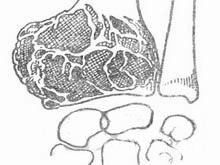

肉眼觀,本瘤常侵犯骨骺線已閉合的長骨端,大多數位於骨骺,早期常為偏心性生長,增大的腫瘤使骨皮質受累而向外膨脹。在腫瘤周圍往往有菲薄的骨殼,乃由骨內、外膜反應性新生骨構成,腫瘤的境界比較清楚。腫瘤內原有松質骨大部分或全部消失,瘤內常有纖維組織或骨性間隔。由於腫瘤組織的溶骨性破壞,常造成病理性骨折。腫瘤組織呈灰紅色,質軟而脆,較大的腫瘤常合併出血及壞死,並伴有囊性變而形成大小不等的空腔,囊腔內含有漿液性或血性液體。晚期病例骨性包殼如果被破壞,則可侵犯軟組織形成腫塊。關節軟骨有抗腫瘤浸潤的作用,關節軟骨下骨間質可完全被破壞,致使關節軟骨失去支持而扭曲變形。

鏡下,腫瘤主要由單核基質細胞及多核巨細胞等兩種細胞組成,間質血管豐富。基質細胞為梭形、卵圓形或圓形,細胞境界不清楚,常見胞漿突起。細胞核較大,染色質量中等,可具有一個核仁。多核巨細胞常較均勻地散布在基質細胞之間,是為本瘤的特點。多核巨細胞的直徑常為30~60μm,核數一般為15~20個,最多可達100個以上,常聚集在細胞的中央。核的形態與單核基質細胞相似。細胞邊界不規則,但分界較清楚,胞漿豐富,略呈嗜鹼性,有時還可見含大量脂類的泡沫細胞。本瘤間質血管豐富,有多少不等的膠原纖維。腫瘤本身無成骨現象,但有時見有類骨組織及新生骨小梁,常見於纖維組織的周圍,可能是一種反應性新骨形成或病理性骨折後形成的骨痂。